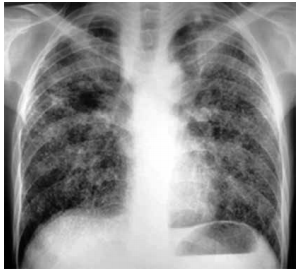

Analise a radiografia de tórax, ilustrada a seguir, e assinale a alternativa que contém a hipótese diagnóstica correta para o caso relatado.